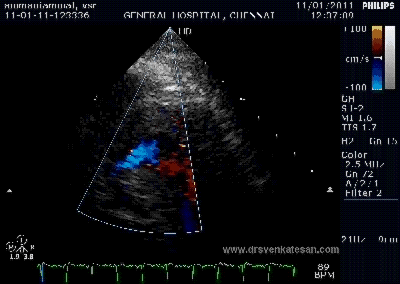

Here is 55 year old women came with extensive anterior MI with lower septal rupture.(She belonged to type 3 of the above scheme)

Note the septal rupture is visible even in 2D Echo

Color flow showing significant shunting from LV to RV.This shunt depends upon the LV contractile function, LVEDP and ofcourse the RV pressure

If there is severe RV dysfunction or bi ventricular dysfunction flow across the defect is inconspicuous.Brisk left to right shunting may be an indirect marker for good LV systolic function and absence of significant pulmonary hypertension.Both imply a better outcome.